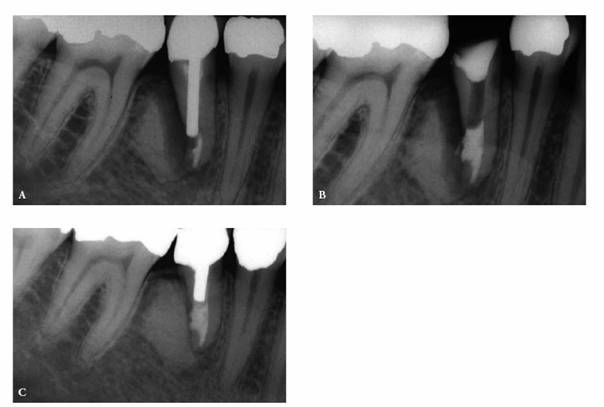

Electric pulp testing with a "mini-tip" through a test cavity may be

the key to making a diagnosis in a tooth with a radiolucency that cannot be

differentiated as either of periodontal or endodontic origin.

One can suspect a necrotic pulp if the reading is negative. Endodontics would

then be the treatment of choice (Figures 19-17A, and 19-17B). If the reading is positive and

there are no pulpal symptoms, periodontal therapy would be indicated (Figures 19-17C 19-17D, and 19-17E). Endodontic treatment may be

required if the root apices are compromised during periodontal procedures (Figures 19-17F, and 19-17G

Figure 19-17A: Mandibular molar with a necrotic pulp. Root canal therapy was instituted.

Figure 19-17B: Ten years following completion of root canal therapy there is a complete bone fill-in. No periodontal treatments were performed on this tooth.

Figure 19-17C: Maxillary central incisor tooth with a vital pulp. Endodontic therapy was not indicated.

Figure 19-17D: A maxillary first molar with a periapical radiolucency.

Figure 19-17E: A gutta-percha point placed in the distal pocket. Pulp testing through an occlusal opening revealed a vital pulp. The cause of the radiolucency was of periodontal origin and therapy followed that course.

Figure 19-17F: Maxillary first molar with an uninflamed vital pulp. There was extensive bone loss surrounding the distobuccal root.

Figure 19-17G: Root canal therapy was performed to allow for the resection of the periodontally involved root.